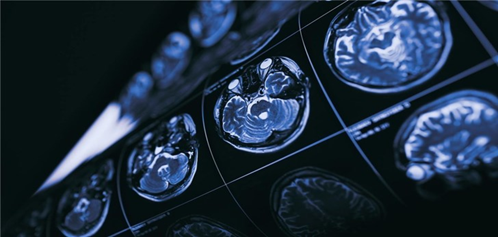

贝利的初步发现证实了先前的预期。在体验反复失重后,一氧化氮水平会上升,这与血液流动增加相一致,尤其是通过供应大脑后部的动脉。这迫使血脑屏障打开,尽管没有证据表明产生结构性脑损伤。贝利等人现在正计划在这些研究的基础上,利用磁共振等成像技术对大脑中的血液和液体流动进行更详细的评估,以证实他们的发现。